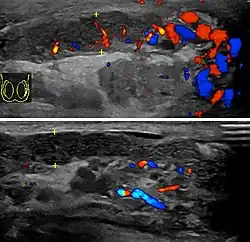

Epididimitis es un término médico que se refiere a una inflamación del epidídimo, la estructura tubular detrás del testículo donde maduran los espermatozoides y que conecta el testículo con los conductos deferentes.[1] Es un trastorno que resulta doloroso en varios grados y se suele acompañar con un enrojecimiento e hinchazón del escroto. La epididimitis es una de las causas más frecuentes de escroto agudo aunque rara vez puede ser una enfermedad crónica. Si el diagnóstico no se logra con la historia médica del paciente y su examen físico, un ultrasonido Doppler puede confirmar el aumento del flujo sanguíneo característico de un epidídimo inflamado.